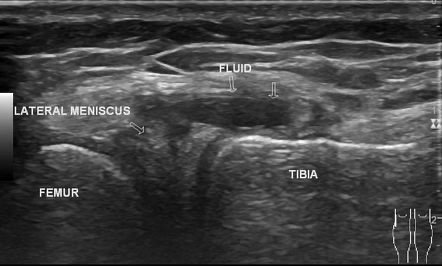

Diagnostic Ultrasound

Some of our clinicians are also fully qualified musculoskeletal sonographers and will carry out a diagnostic ultrasound scan of your knee.

Many of our clinical specialist physiotherapists are able to perform the scan as part of your assessment (please request when booking if you would like to have diagnostic ultrasound as part of your assessment).

Ultrasound is unable to assess the deep portion of the meniscus, however, it can detect more superficial tears and is also an effective tool to assess for any swelling and inflammation in the knee. Ultrasound can also visualise meniscal cysts and other structures in the knee such as the medial and lateral collateral ligaments and the surrounding tendons. Meniscal cysts are small fluid-filled pockets that arise from the meniscus. These can occur secondary to a tear.